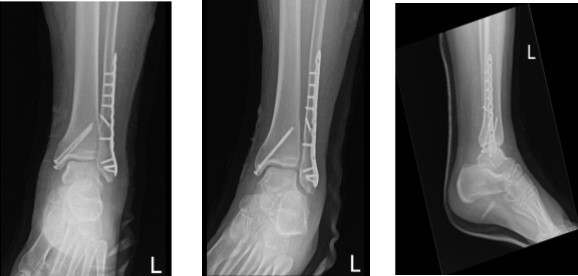

Preop antibiotics were already given. A lateral incision was given centered over the fracture. The fracture was opened and washed. The fracture was reduced and fixed with the interfragmentary screw inserted. Neutralization plate was applied over the lateral malleolus with the distal and proximal screws with a combination of locking and nonlocking screws finding it in acceptable position.

Pictures were taken and saved. Now, the attention was diverted to the medial malleolus. A hockey stick incision was driven along the medial malleolus. Fracture site was reached and clean. There was a periosteum going into the fracture sites, which was excised using a blade.

The fracture was opened and washed using irrigation fluid. The fracture was reduced and held with a clamp. The two guidewires were inserted anterior and posterior to the clamp and the fracture was held in place.

Medial malleolus was performed and two malleolar screws x60 mm were inserted over the guidewires. Final tightening was done after removal of the guidewires. Pictures were taken and found to be in acceptable positions. The pictures were saved.

Left ankle X-ray complete 3 or more views

After 2 months the patient was seen in the office for his follow up checkup, he is in post splint and NWB-PWB. He denies fever, chills, he is elevating and icing the ankle, his pain control has been improving.

And he is able to bear some weight on it. With the continued follow up checkup the patient showed progress from time to time he visits the office. He gets well after the surgery and with the help of continuing physical therapy.